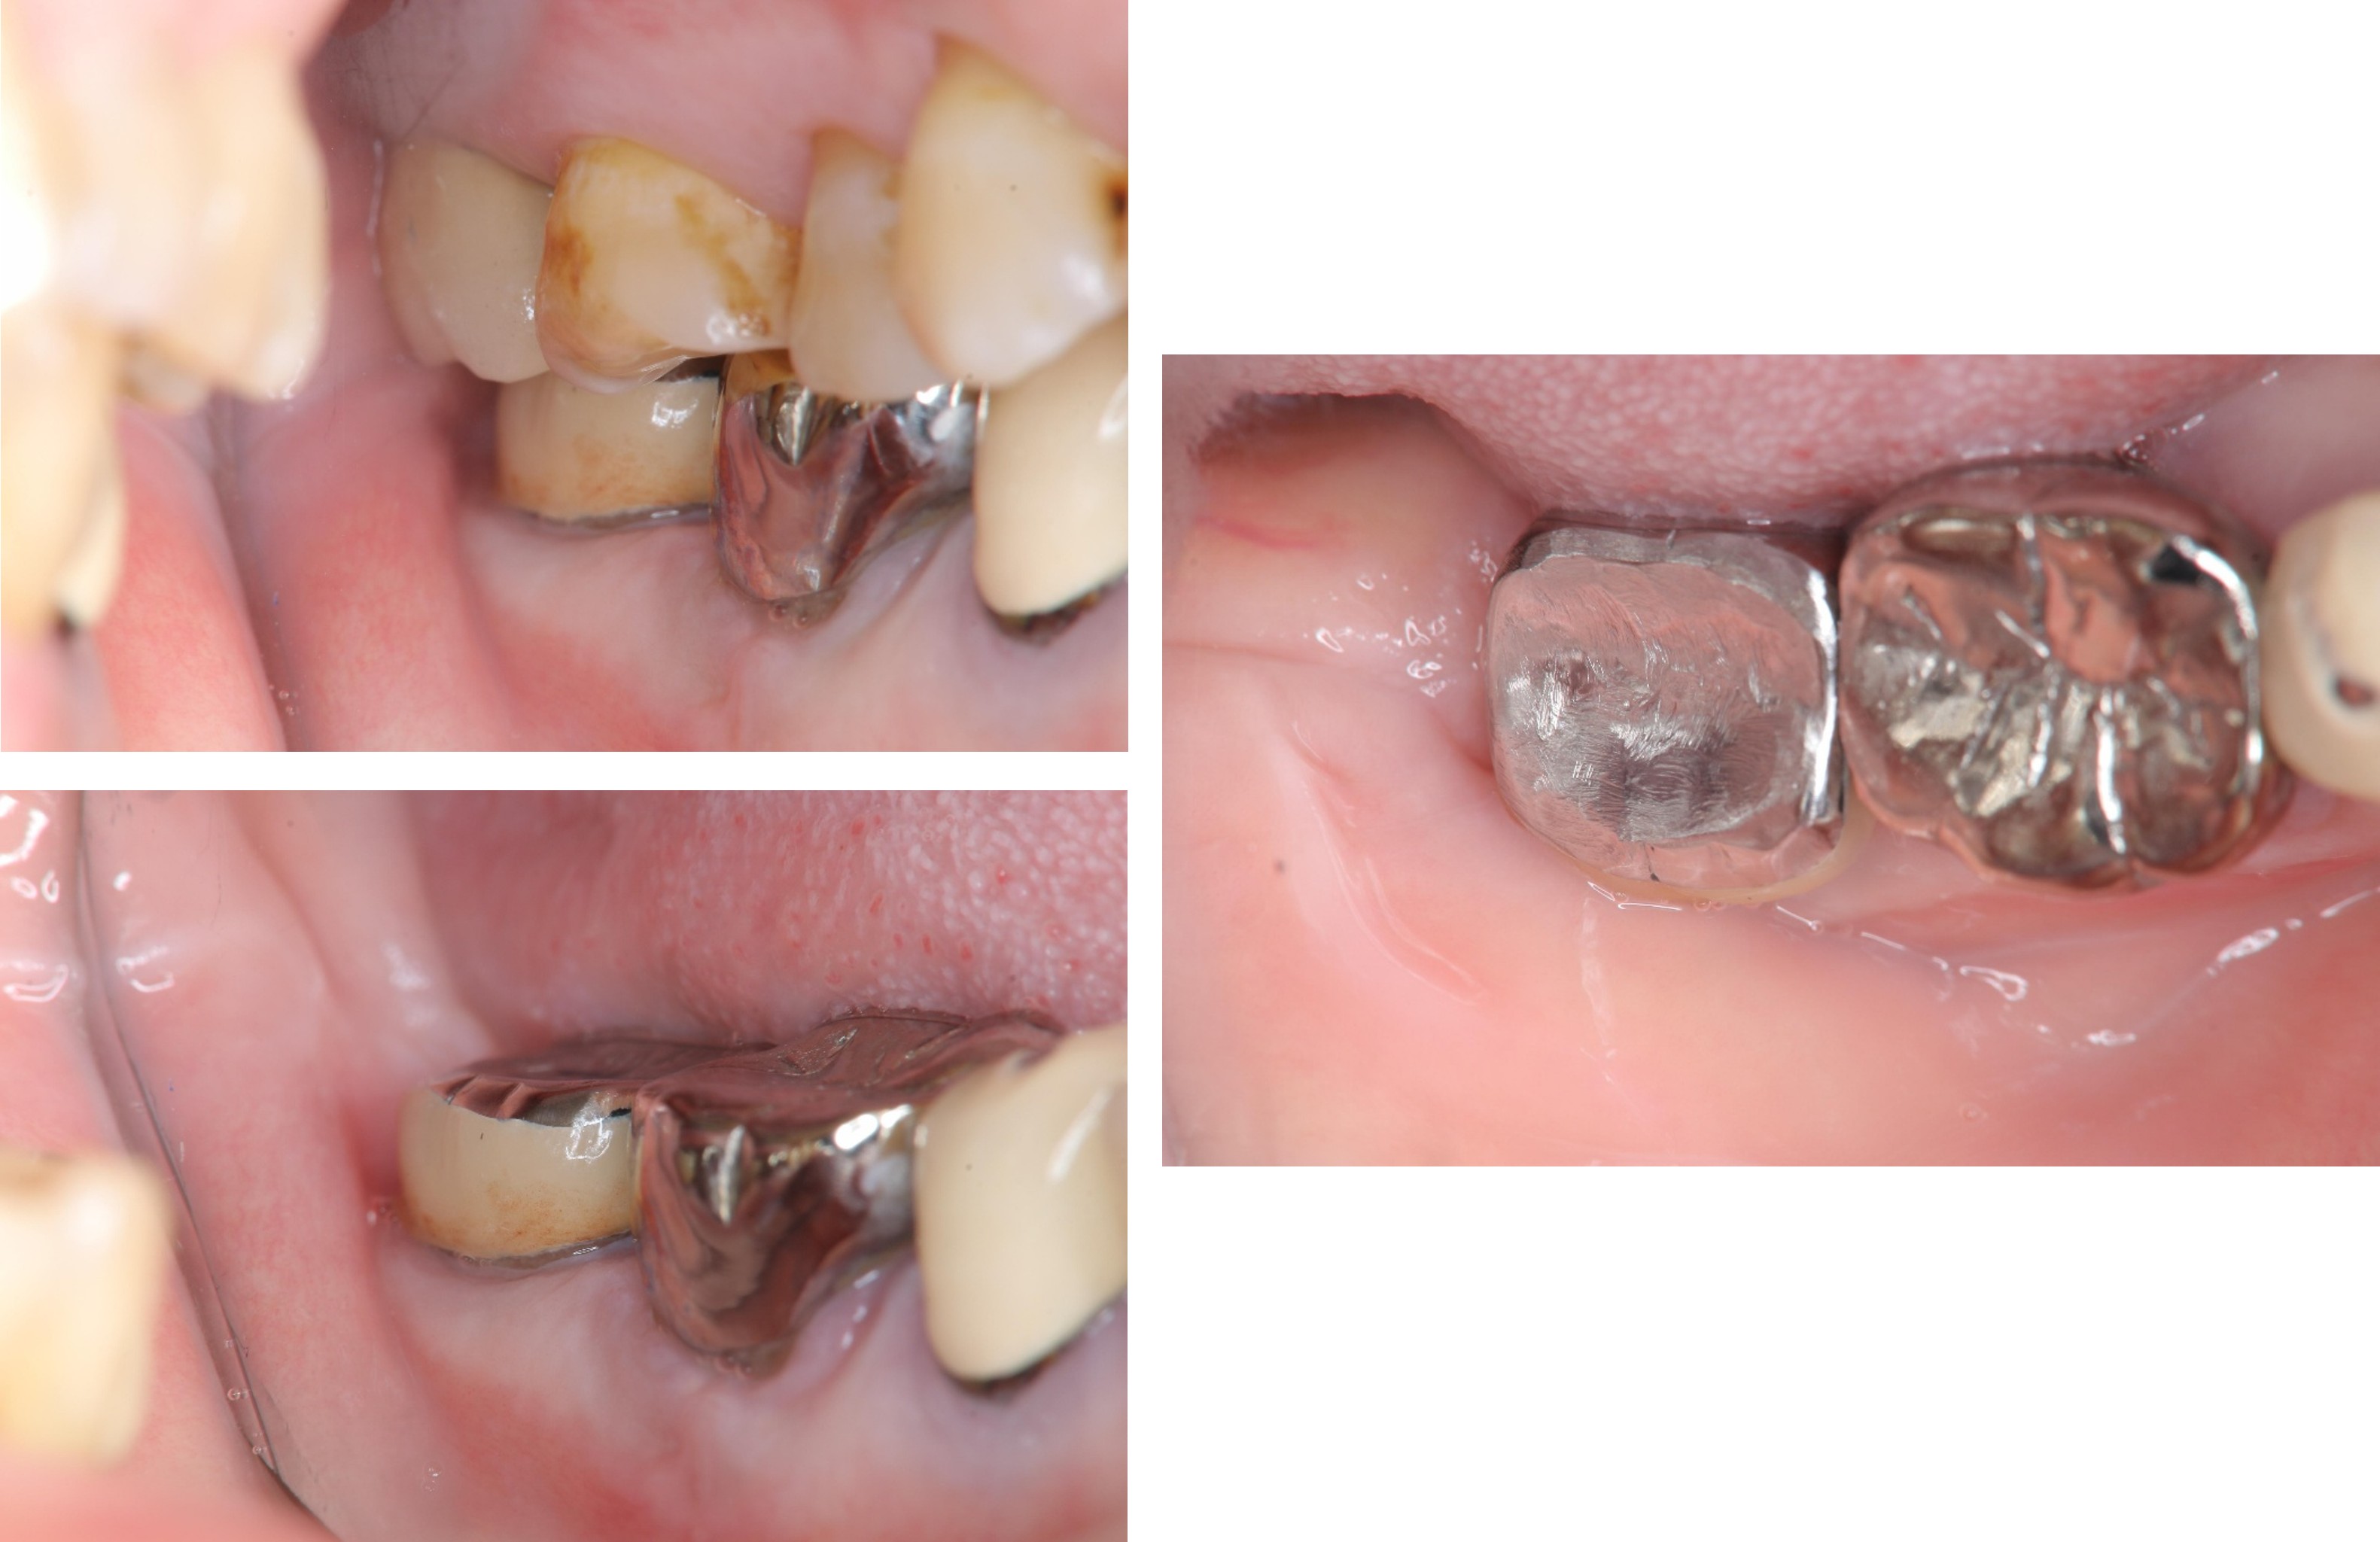

治療前,蛀牙齒質破壞

治療前,患者已接過根管治療

水雷射牙冠增長手術

因受力考量,製作金屬燒付瓷牙